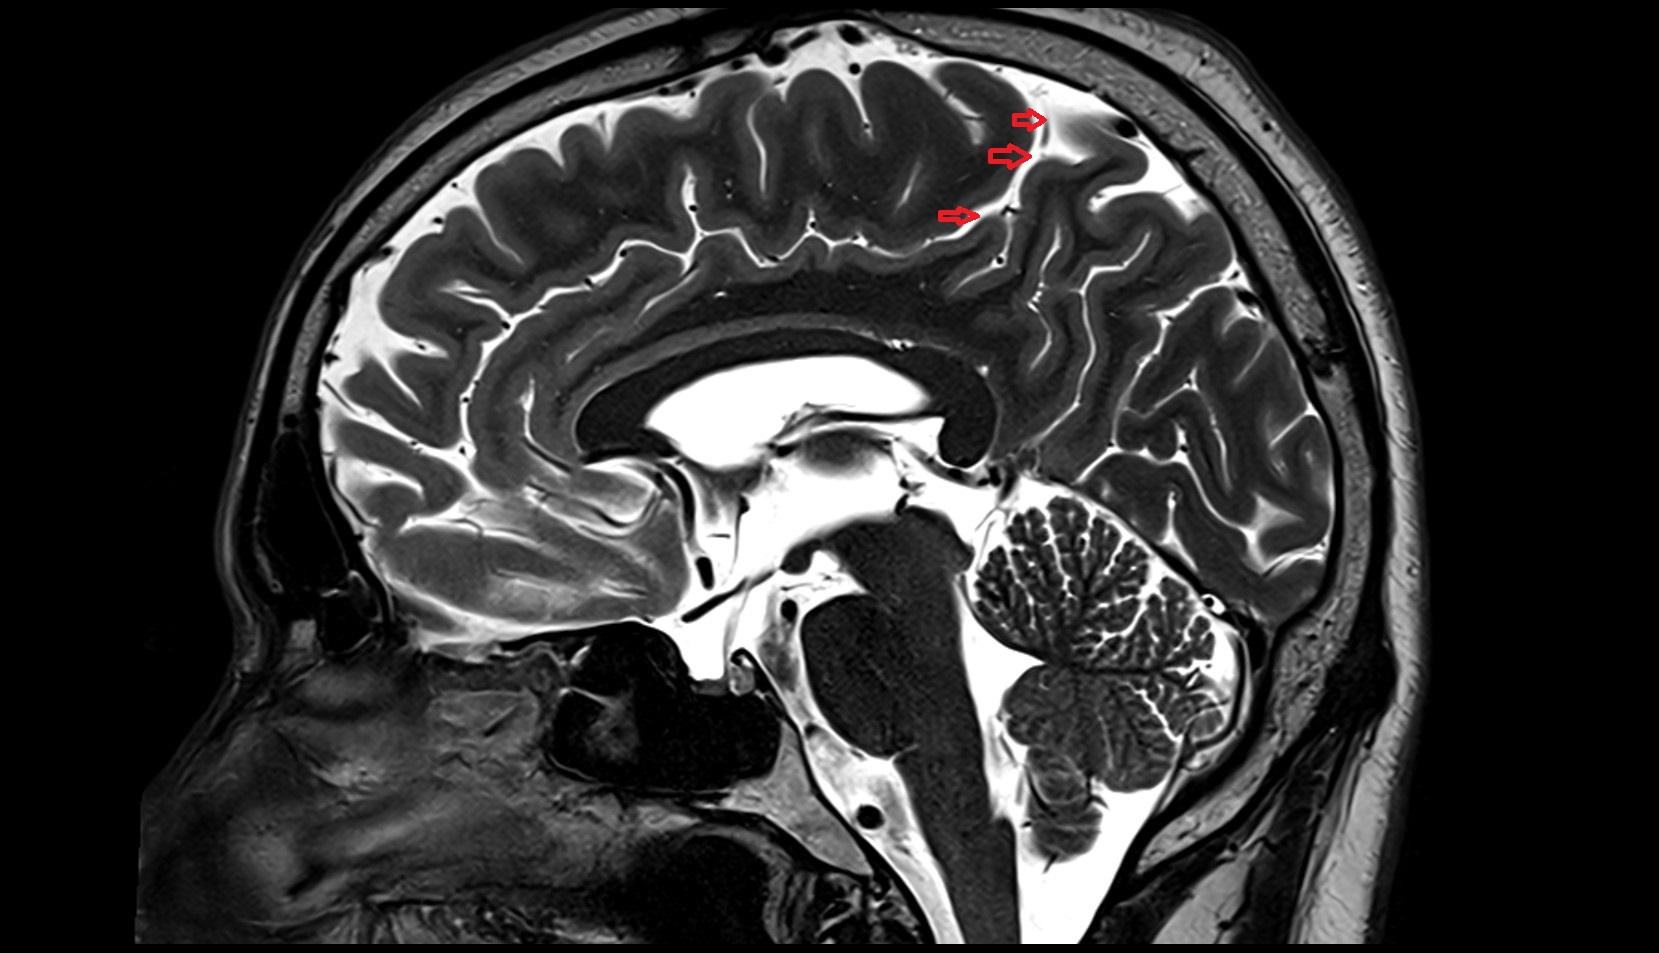

- Cingulate sulcus

- Parietooccipital sulcus